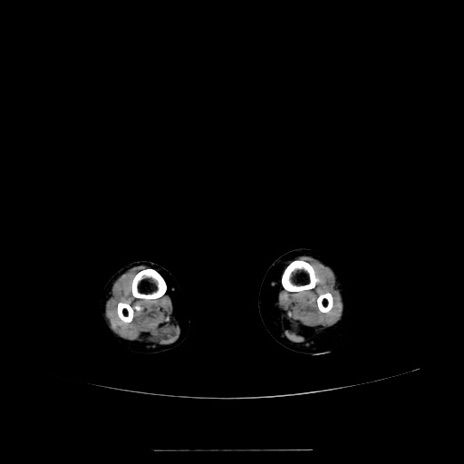

症例5(横断像)

症例

【症例】70歳代女性

【主訴】お腹が張る

【現病歴】1週間くらい前から腹部膨満の自覚あり。昨日夜から増悪したため、本日救急外来受診。

【既往歴】なし

【身体所見】意識清明、BT 36.5℃、BP 165/106mmHg、HR 80bpm、SpO2 98%、腹部:膨満、軟、自発痛・圧痛なし、触診にて不快感あり、腸蠕動音:減弱

【データ】WBC 12600、CRP 1.04